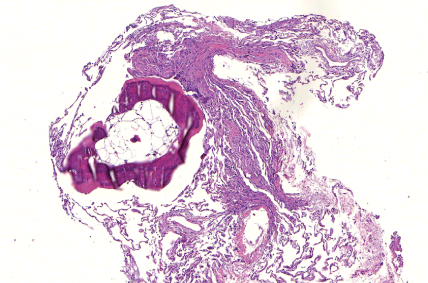

An 81-years-old patient presented himself with dyspnea on exercise and dry cough, for 3 months. He was being treated to Waldenström's Macroglobulinemia in the prior 6 months and had non-requiring dialysis chronic renal failure as a consequence of the disease. High-resolution CT scan showed pulmonary micro-nodules with some predominance in the bronchial-vascular axis (Figure 1). Due to the findings in the CT scan and the high prevalence of the disease in Brazil, the patient was being treated empirically as having miliary tuberculosis and presented several side effects following the therapy, such as liver toxicity and Steven-Johnson's dermatitis. He was then referred to our service and submitted to transbronchial biopsy that showed the presence of pulmonary ossification in the nodular form (Figure 2), quite possibly secondary to renal failure or to amyloidosis. Tuberculosis drugs were removed, and the patient improved the respiratory symptoms with further therapy to Waldenström's Macroglobulinemia and diuretics [1,2].

Figure 2: Transbronchial biopsy demonstrating pulmonary metaplastic ossification, adjacent to normal lung alveoli (right) (H&E).